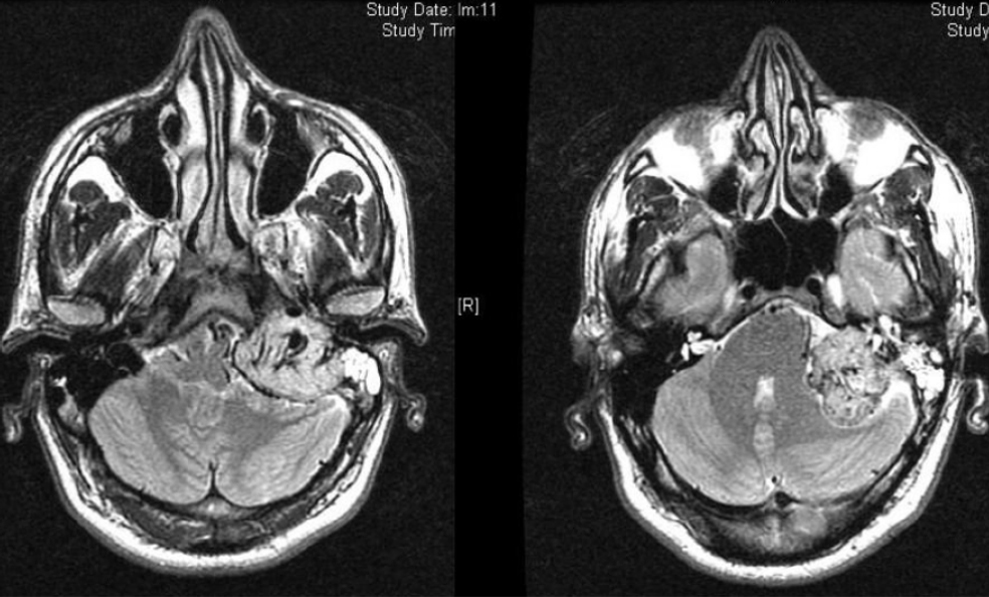

In questa immagine quattro tra i pazienti operati dal prof. Salvinelli.

A destra

nella Risonanza magnetica (RMN) preoperatoria si vede il tumore con colore bianco che si espande nel cervello

Al centro

si vede la RMN post operatoria.

A sinistra

la TAC postoperatoria.

Si nota che con queste tecniche la patologia viene rimossa e le strutture cerebrali vengono massimamente rispettate.